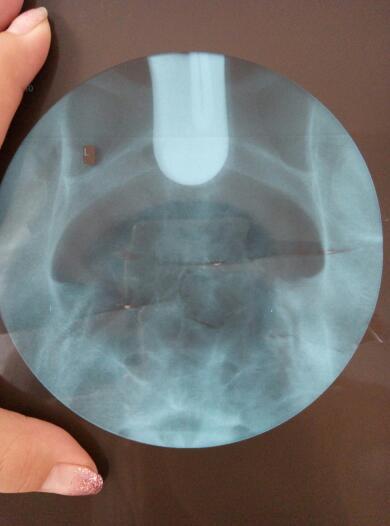

帮我看看,什么情况,还能自然受孕吗?不做手术吃药能解决吗?好人一生平安 点击展开 匿名用户 2016-06-01 09:40 满意回答 根据你的输卵管造影检丛遮查结果显示,筝扬露应该考虑是属于输卵管阻塞等原因引起的症且脑状,应该是比较难自然受孕的,应该积极进行治疗。可以考虑进行输卵管通水治疗的。必要时可以考虑进行宫腔镜,三镜一丝等手术治疗。 太阳荣华医师 2016-06-01 10:03 宝宝知道提示您:回答为网友贡献,仅供参考。 相关问题 请问这是什么?好人一生平安帮我看看吧 朋友们懂得人帮我看看,像这样的报告我想做人工受孕的机率大吗? 一个朋友结婚四年多了,他老婆不孕 现在医院要她做手术治疗 先吃了催排药打算现让他们试一个月自然受孕